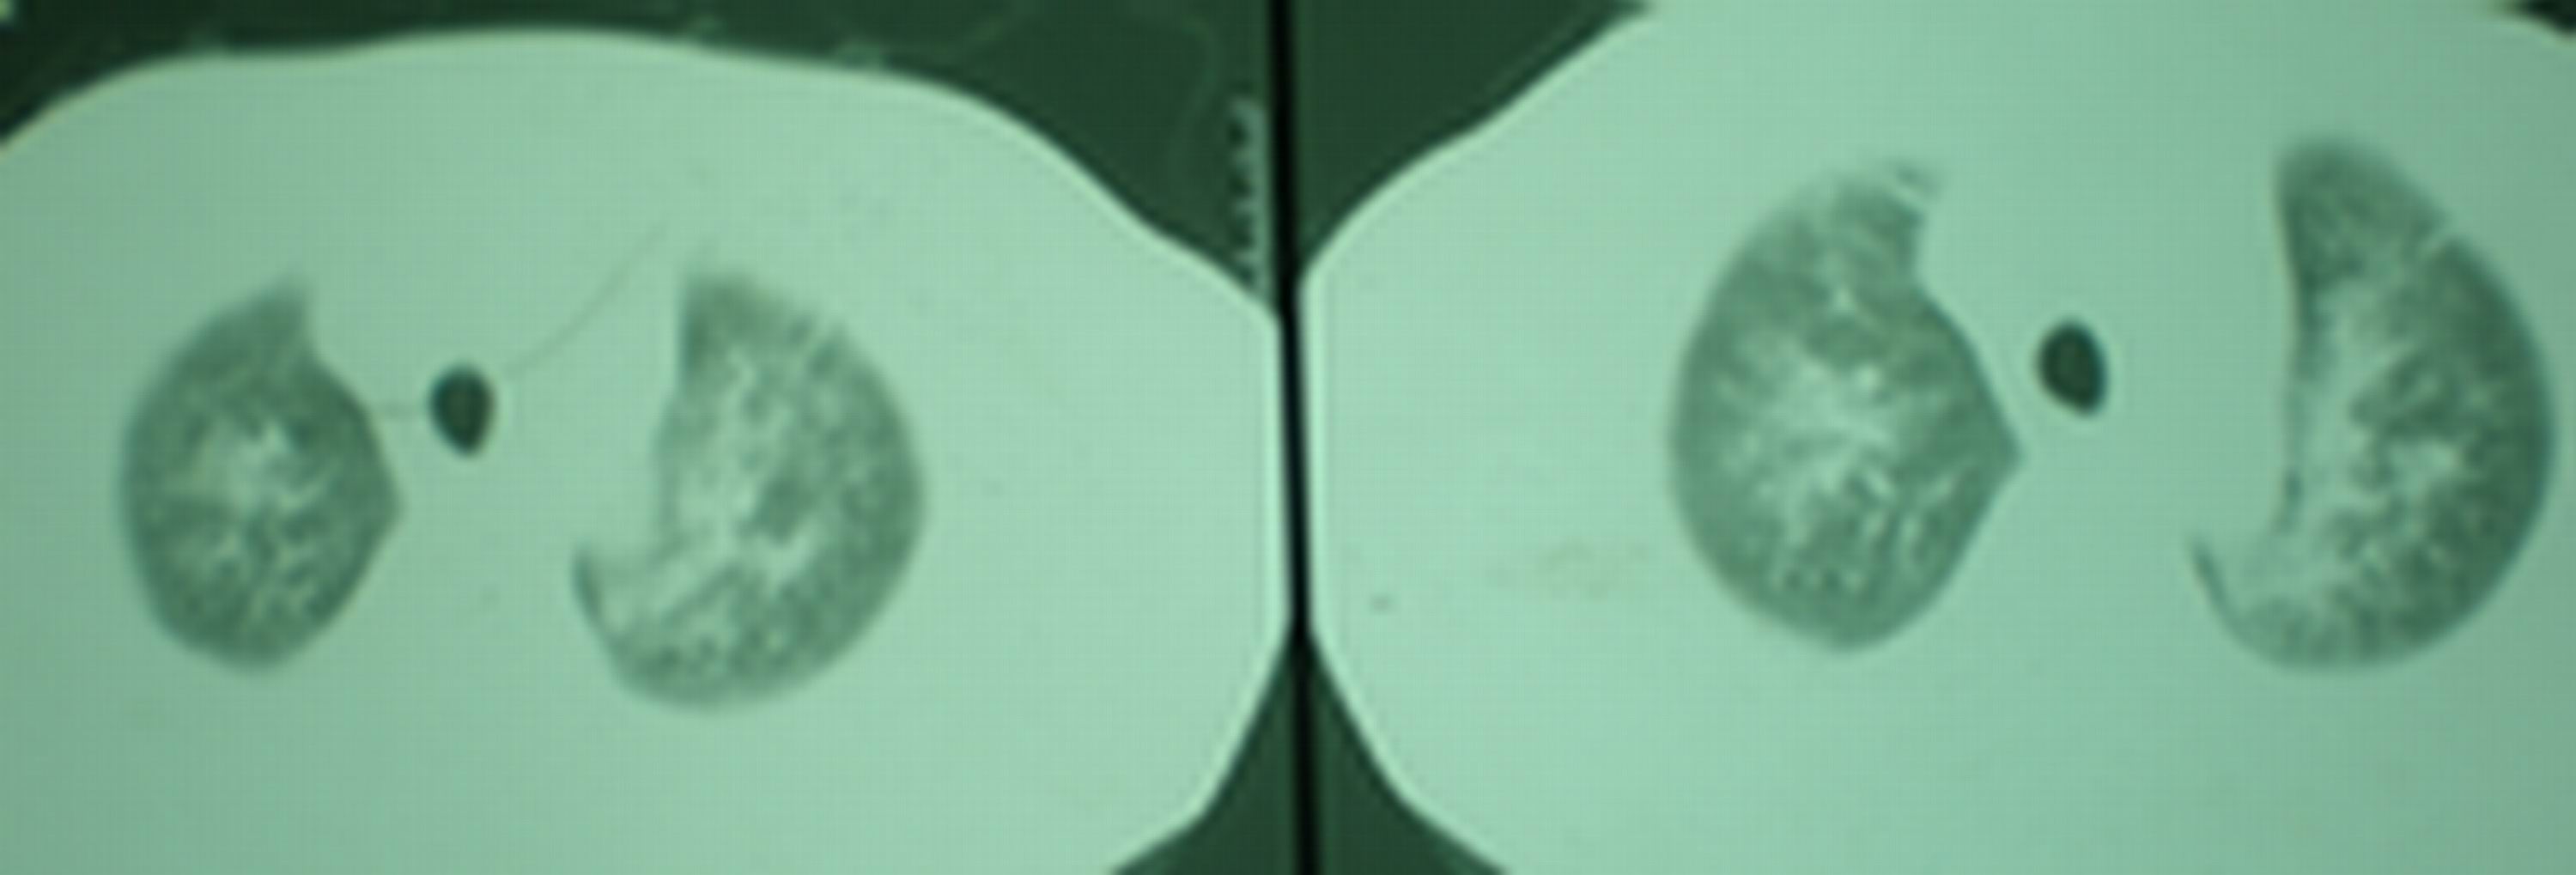

2008年11月18日今天的ct片

2008年9月18日ct片

2008年9月8日ct片:

[face=宋体]显然上级医院进行了抗结核,抗真菌,抗炎等治疗,目前病人肺内病灶基本消失,双侧胸腔积液,右侧积液量有吸收,抗结核一个多月,现在病人疑问,结核的诊断是否有疑义,抗结核是否继续,因为那个毕竟副作用大。[/face]

机遇性感染!不除外急性肺水肿!

我仔细看了下病人的出院小结,当时情况危急,诊断里有1型呼衰。心包周围的是脂肪密度。结合三次ct扫描的图象分析,个人认为:1、病人目前肺部病灶基本消失,双侧胸腔内少量积液,抗结核治疗才一个多月,就算是结核,抗结核治疗有效果,为何效果如此好,一点纤维灶的痕迹都没有呢,再就是患者做过气管镜检查及活检、痰检均未找到结核的证据。所以不支持结核的诊断。

2、结合现在的ct片,考虑:肺水肿及真菌感染,双侧胸腔积液。

急性呼吸窘迫综合征,肺水肿,与激素减量太快有关.双侧胸腔积液.

机遇性感染。双肺实质满布。且以肺门周围为主。不象结核。